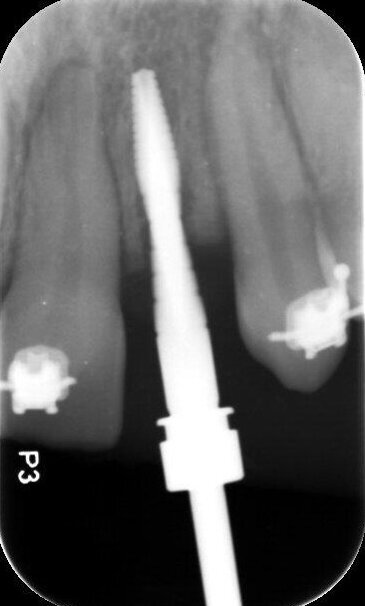

In deze casus is indertijd voor tissue level-implantaten gekozen en na ongeveer achttien jaar in functie is de esthetiek, mede door de vorm van de cuspidaten en het zichtbaar worden van de implantaten, discutabel te noemen (afbeelding 1 en 2).